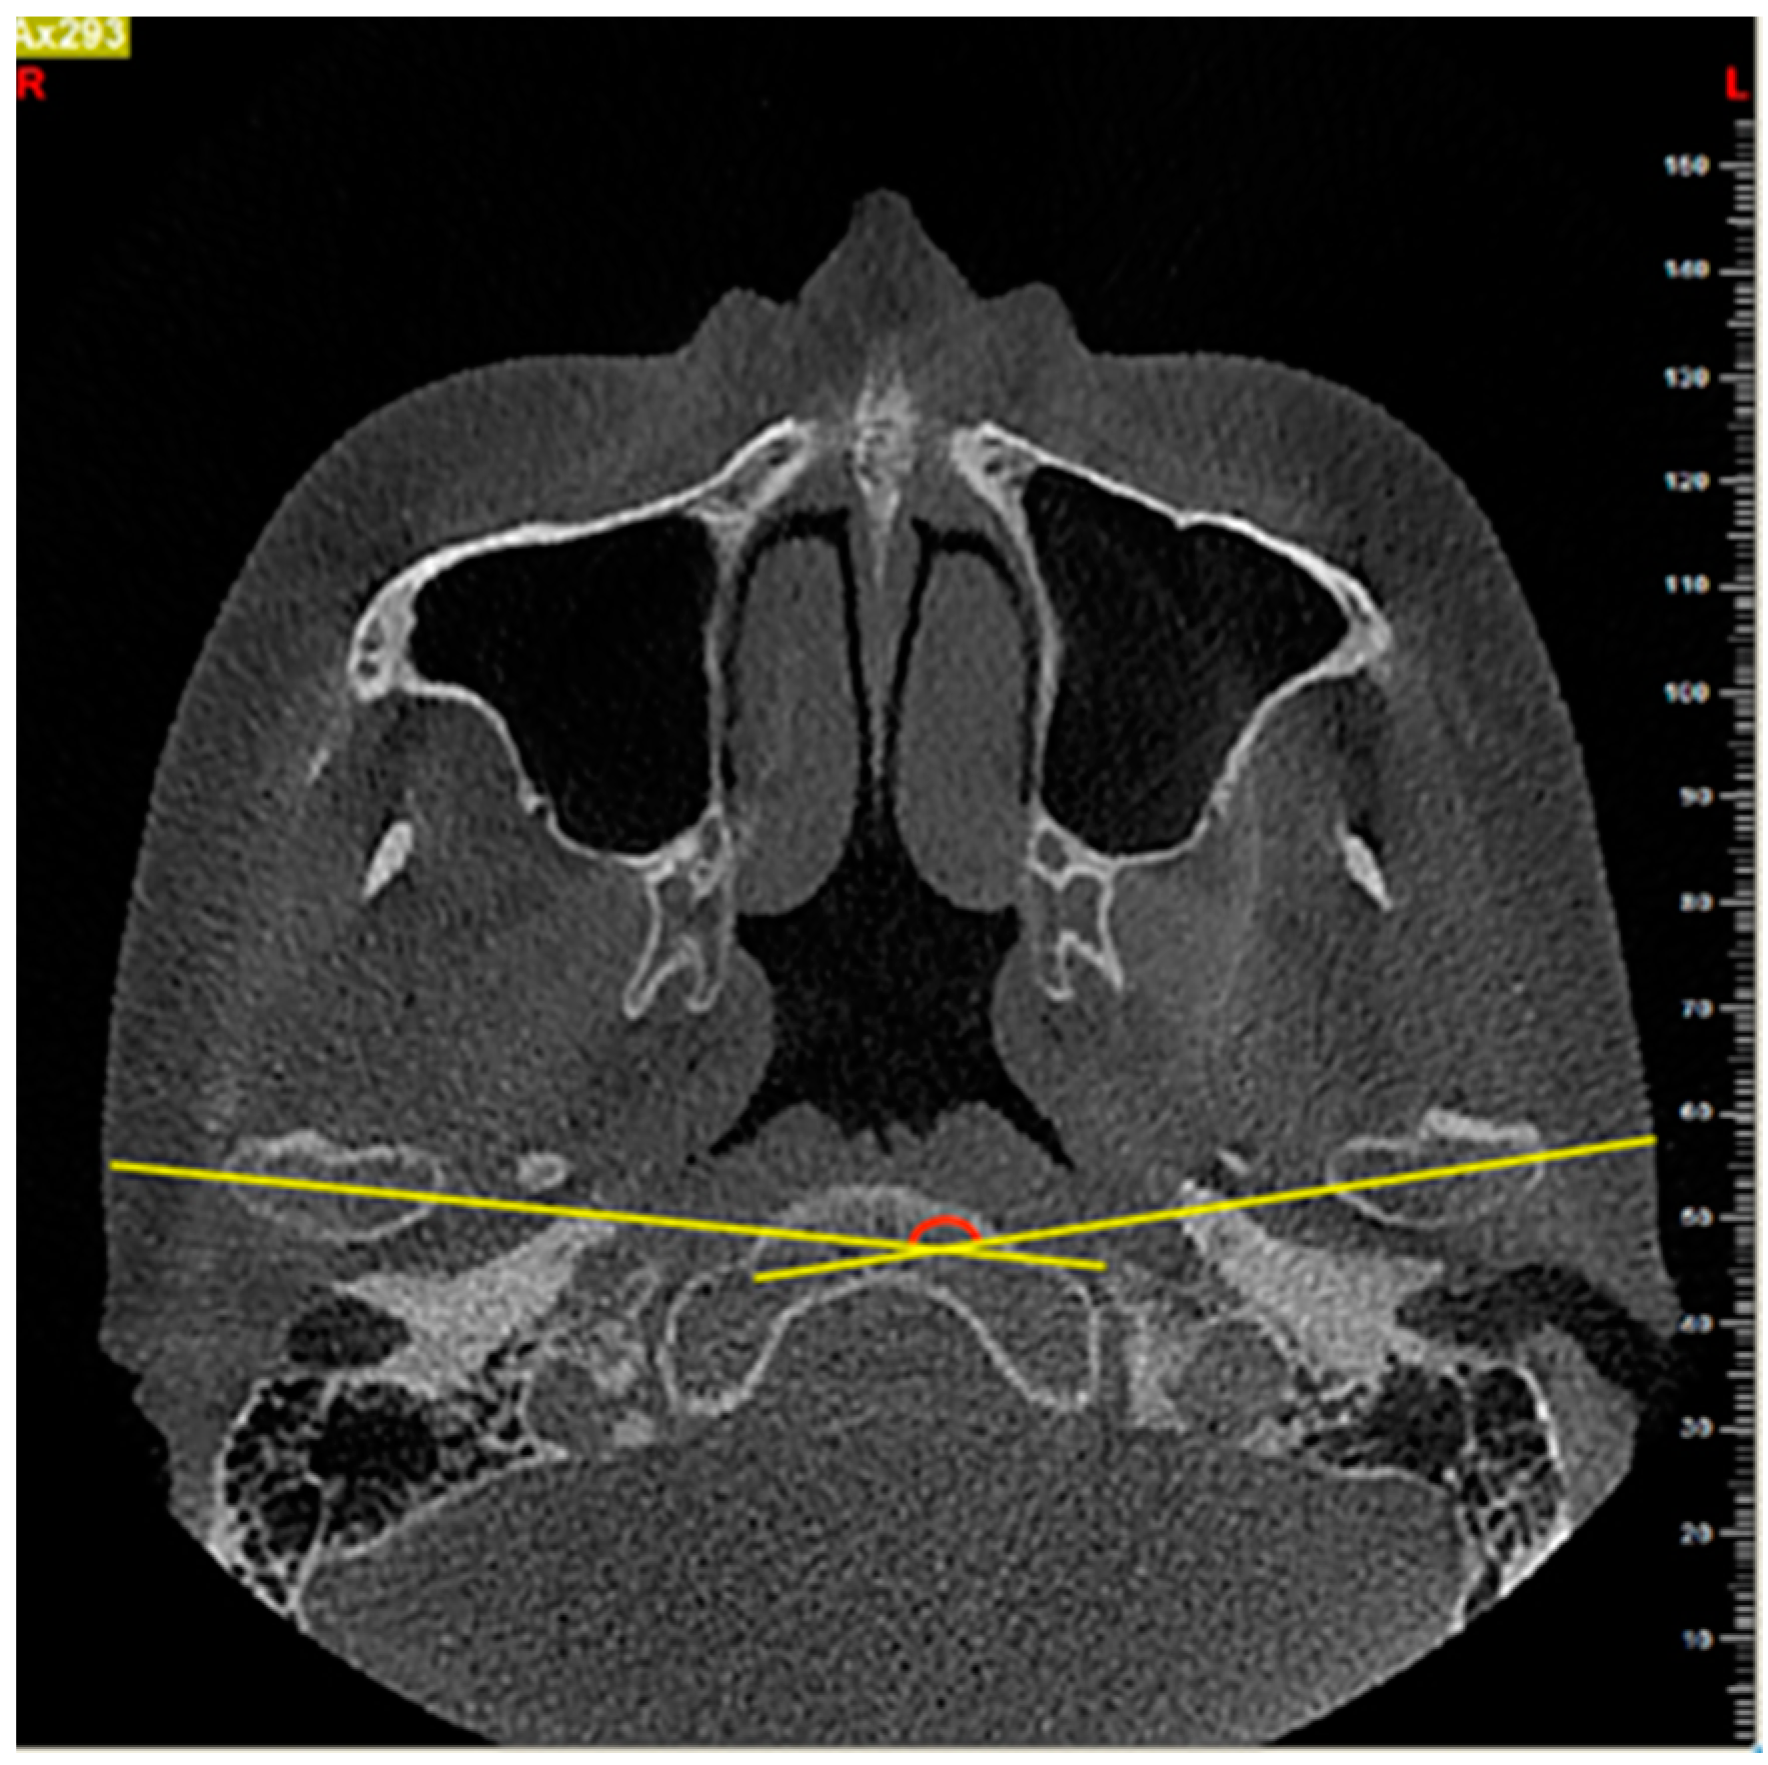

2.4. Measurements